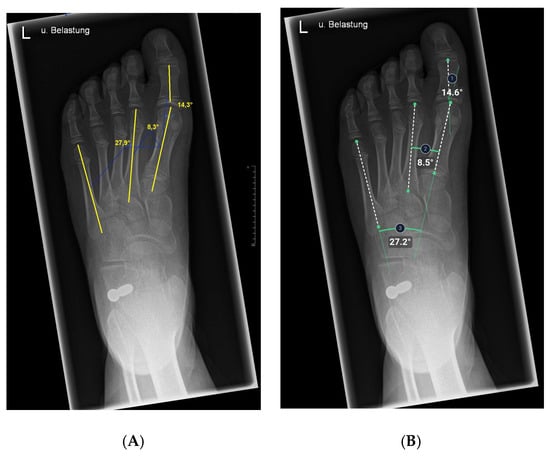

2.5. Anatomic Definitions

At this point, the AI system used was able to measure three angles each of the lateral and dorsoplantar projection (Figure 2 and Figure 3). The talus-1st metatarsal angle and all three angles in the dorsoplantar plane were defined by the intersection of axes. Axes for angle measurements were mechanically defined as lines connecting the center of the bone head and the center of the bone base [30,31]. The talus-1st metatarsal angle was determined by the intersection of the axis of the first metatarsal and a line intersecting the head and neck of the talus [23,32]. (Figure 2). The medial arch angle was measured by a line joining the lowest point of the medial sesamoid with the lowest point of the talonavicular joint and from there a line to the lower edge of the calcaneus [23,32]. The calcaneus inclination angle was defined by the intersection of a line drawn from the inferior cortex of the calcaneus to the inferior corner of the calcaneus, which belongs to the calcaneocuboid joint with the horizontal axis [23]. Physiological values were −4° to 4 ° for the talus-first metatarsal angle. For 8-year-old children, 5 ° was given as the standard values at this age [6]. The normal value was 120 ° to 130° for the medial arch angle and 11 ° to 24 ° for the calcaneal inclination angle on X-rays of immature children [6,33].

The hallux valgus angle is determined by the axis of the first metatarsal bone that of the proximal phalanx [23,32].

Having intersected the axis of the first metatarsal bone with the axis of the second metatarsal bone, the 1st-2nd metatarsal angle was obtained [23,32].

The intersection of the axes of the 1st metatarsal and 5th metatarsal resulted in the third and last angle examined, the 1st-5th metatarsal angle [23].

Figure 2. Illustration of talus-1st metatarsal angle, medial arch angle, and calcaneus inclination angle measurements on X-ray images in the lateral plane. (A) Manual measurement exemplary. The same X-ray image was processed by the AI. (B) Angles calculated by AI.